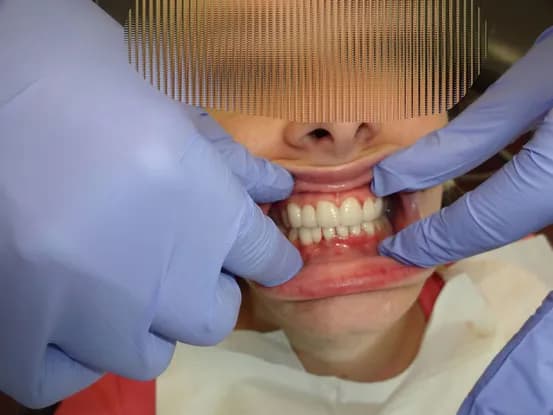

Case 1

26 year old female with teeth crowding and slight overbite. Patient refused to have 2 years of orthodontics. Gingivectomy, cosmetic bonding, extraction, Zoom Bleaching, and 12 units of e-max restorations performed.